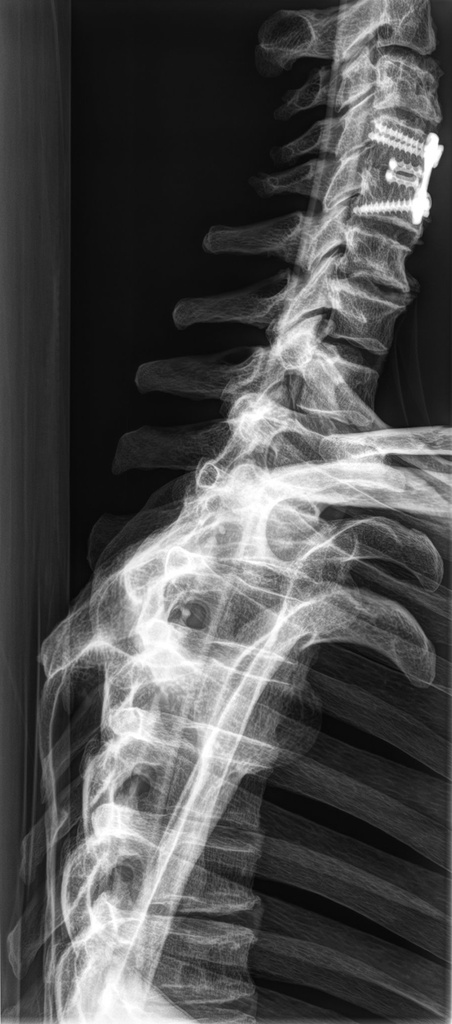

Dieses weltweit einmalige Phantom bietet erstklassige Übungsmöglichkeiten für die Lagerungs- und Einstelltechnik in der Projektions-Radiographie und gehört eigentlich zur Grundausstattung jeder Röntgen-Ausbildungsstätte. Das Phantom enthält ein natürliches menschliches Skelett sowie die Umrisse von Kehlkopf, Lunge, Herz und Nieren (Organe erscheinen als Schatten auf den Röntgenbildern), dadurch können mit dem Phantom echte Röntgenaufnahmen wie beim Patienten gemacht werden. Durch die Verwendung des echten Skeletts können Leitstrukturen im Knochen erkannt werden, was bei Kunststoffskeletten nicht möglich ist. Bei der Montage des Phantoms wird besonderer Wert auf die Darstellung der Gelenkspalte gelegt. Die Gelenke sind voll beweglich montiert, und ermöglichen die Lagerung in den normalen Röntgenpositionen (z.B. Froschposition, Pro- und Supination des Unterarms). Die Arme können nach oben bewegt werden, so dass das Modell auch für alle knöchernen Untersuchungen im CT verwendet werden kann. Bei jedem Phantom handelt es sich um ein handgefertigtes Unikat, welches sich in Größe und Ausführung unterscheiden kann. Je nach Modell können pathologische Befunde vorhanden sein, die äußere Erscheinung kann sich je nach Größe des Modells unterscheiden. Die neue Ausführung dieses Modells wurde in Zusammenarbeit mit einer namhaften deutschen Schule für Med. Techn. Radiologieassistenten komplett überarbeitet und erfüllt alle Anforderungen für die Ausbildung. Der Verkauf dieses Phantoms erfolgt nur gegen Nachweis der medizinischen Verwendung. Natürliche Größe.